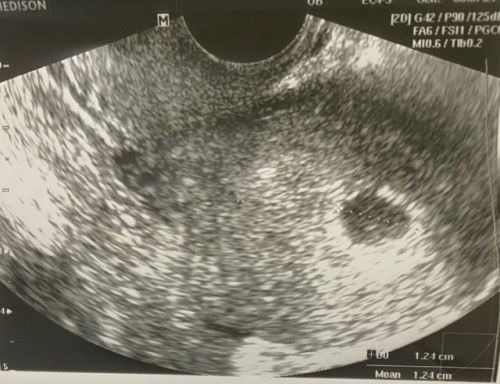

6w3d masih nampak kantung

Hai mommies, tadi baru pergi scan. Buat tvs scan. Kandungan usia 6w3d, Dr bgtau nampak kantung dalam rahim. Baru rasa lega sikit lps tahu kandungan dlm rahim. Buat details scan jugak utk scan benda lain, alhamdulillah, no ovarian cyst. Not ectopic pregnancy. And kilang telur kedua2 sihat dan elok. Right and left ovary. Cuma kena tunggu 2 minggu lg utk nampak baby. Baby kecik lg so nampak kantung aje. Ade ke mommiea kat luar sana dh 6minggu masih nampak kantung aje. Share2 ya. Tq mommies..